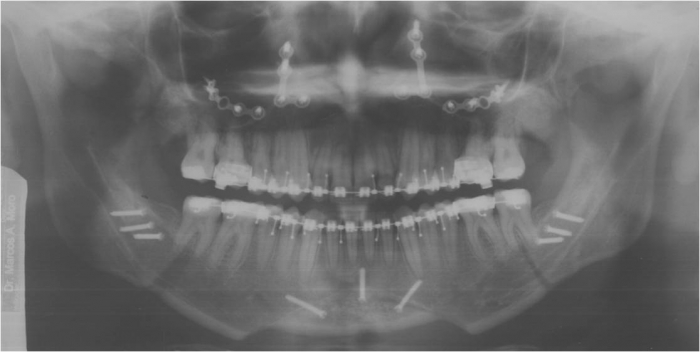

Raio x panorâmico após a cirurgia